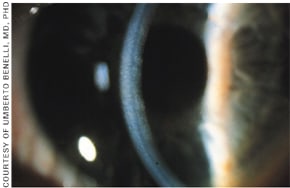

Fuchs' Endothelial Dystrophy is unusual in that it has a late onset usually not observed or affecting the patient until the fifth decade. In some cases it has a dominant mode of inheritance with incomplete penetrance. Fuchs' dystrophy is characterized by guttata, which are refractile excrescences on the posterior cornea (Figure 6). Guttata form secondary to abnormal functioning endothelial cells and can occur as the result of aging, trauma or inflammation.

Figure 6. Guttata in direct and proximal illumination in Fuch's Endothelial Dystrophy.